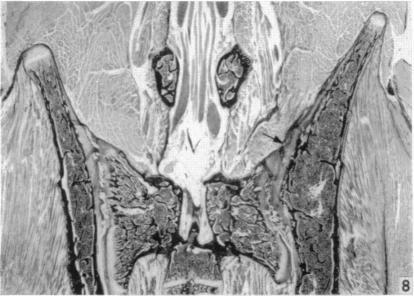

An experimental study of pelvic growth in the rat.

J Anat. 1958 Jul;92(3):483-8.